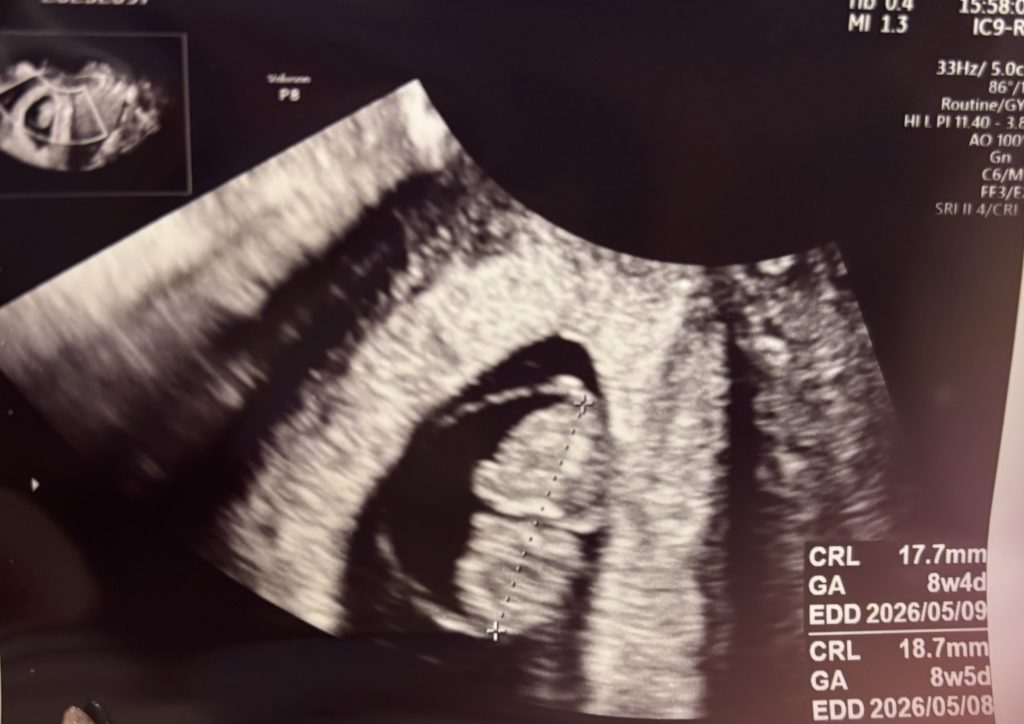

エコー写真(妊娠6週0日)

胎嚢はしっかり確認が出来ました。

子宮内に胎嚢があることが確認出来たので、子宮外妊娠の可能性は無くなりほっとしました。

丸い輪っかの様なものが、リングと呼ばれる卵黄嚢で、黒い影の様なものが、胎嚢です。

胎嚢・・・赤ちゃんを育てる袋

卵黄嚢・・・妊娠早期の胎児に対する栄養分

この頃の赤ちゃんの大きさは5ミリ〜7ミリ程度。

エコーで確認できる大きさでは無いので、早く赤ちゃんの姿かたちが見たい気持ちでいっぱいになりました。

正直、胎嚢だけの確認だと、あまり妊娠している実感がわかなかったです。